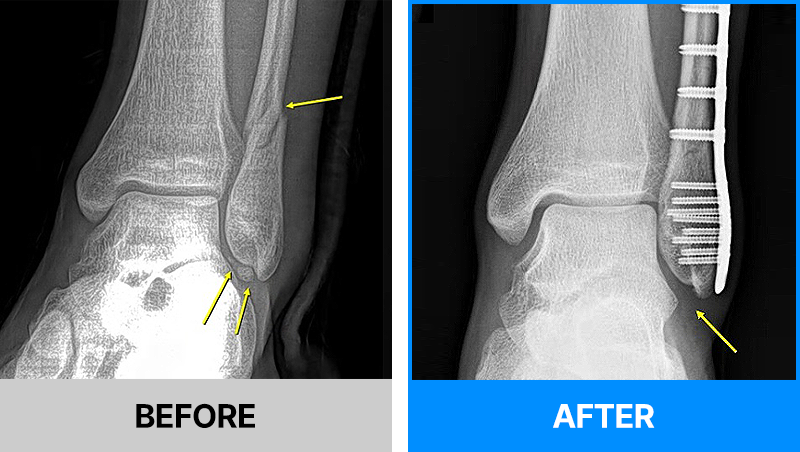

왜 당일 입퇴원 수술일까요?

오래 입원할 필요가 없기 때문입니다.

서울거탑정형외과에서는 전신마취, 척추마취가 아닌

국소부분마취(신경차단) 및 수면 마취를 통해 수술을 시행합니다.

수술 가능 여부 확인은 대표원장과의 진료가 필요합니다.